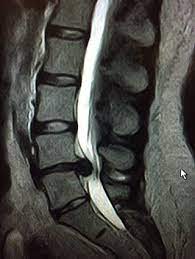

Nach der Bandscheiben-OP sollten Patienten keinesfalls eine reine Schonhaltung einnehmen. Grund für die Beschwerden ist dass der innere Kern der Bandscheibe austritt und auf Nerven am Spinalkanal drückt. Je lockerer sie werden umso eher kann dein Körper den Schmerz abstellen auch wenn das Röntgenbild sichtbare Veränderungen zeigt und schon ein Vorfall diagnostiziert wurde.

Bei einem Bandscheibenvorfall in der LWS kommt es zu Schmerzen die typischerweise akut einsetzen beim Druck auf die Spinalnerven die aus dem Rückenmark herausziehen. Die Schmerzen die vom LWS -Bandscheibenvorfall ausgehen strahlen dabei oft in die Regionen Po Beine Knie und Füße. Was ist wenn es einen Bandscheibenvorfall zeigt. Die Schmerzen beginnen im Bereich des unteren Rückens und werden von den meisten Betroffenen als ziehend. Bei einem Bandscheibenvorfall lohnt es sich Muskeln und Faszien zu entspannen. Studien zeigen dass körperliche Aktivität die Beweglichkeit verbessern kann. Ich war sehr nervös weil mir keiner sagen konnte wie sich das ganze anfühlt. Durch Husten und oder Niesen werden die Symptome verstärkt. Denn durch längeres Liegen werden Muskeln und Knochen schwächer was zu weiteren Problemen führen kann.